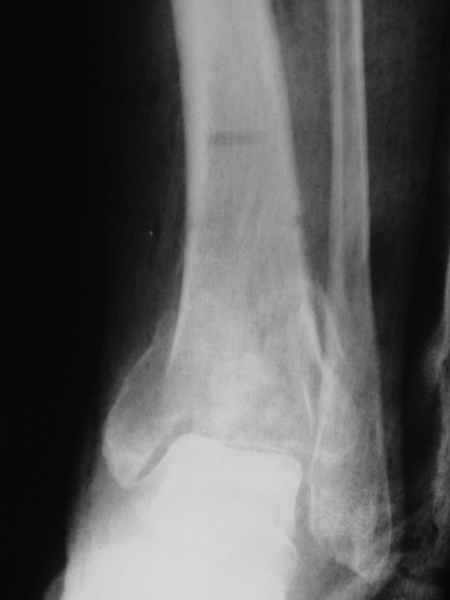

Конечно. Но если нет повода трогать подтаранный сустав, может, делать не через него, а так?

Кликните для загрузки файла ankle.jpg